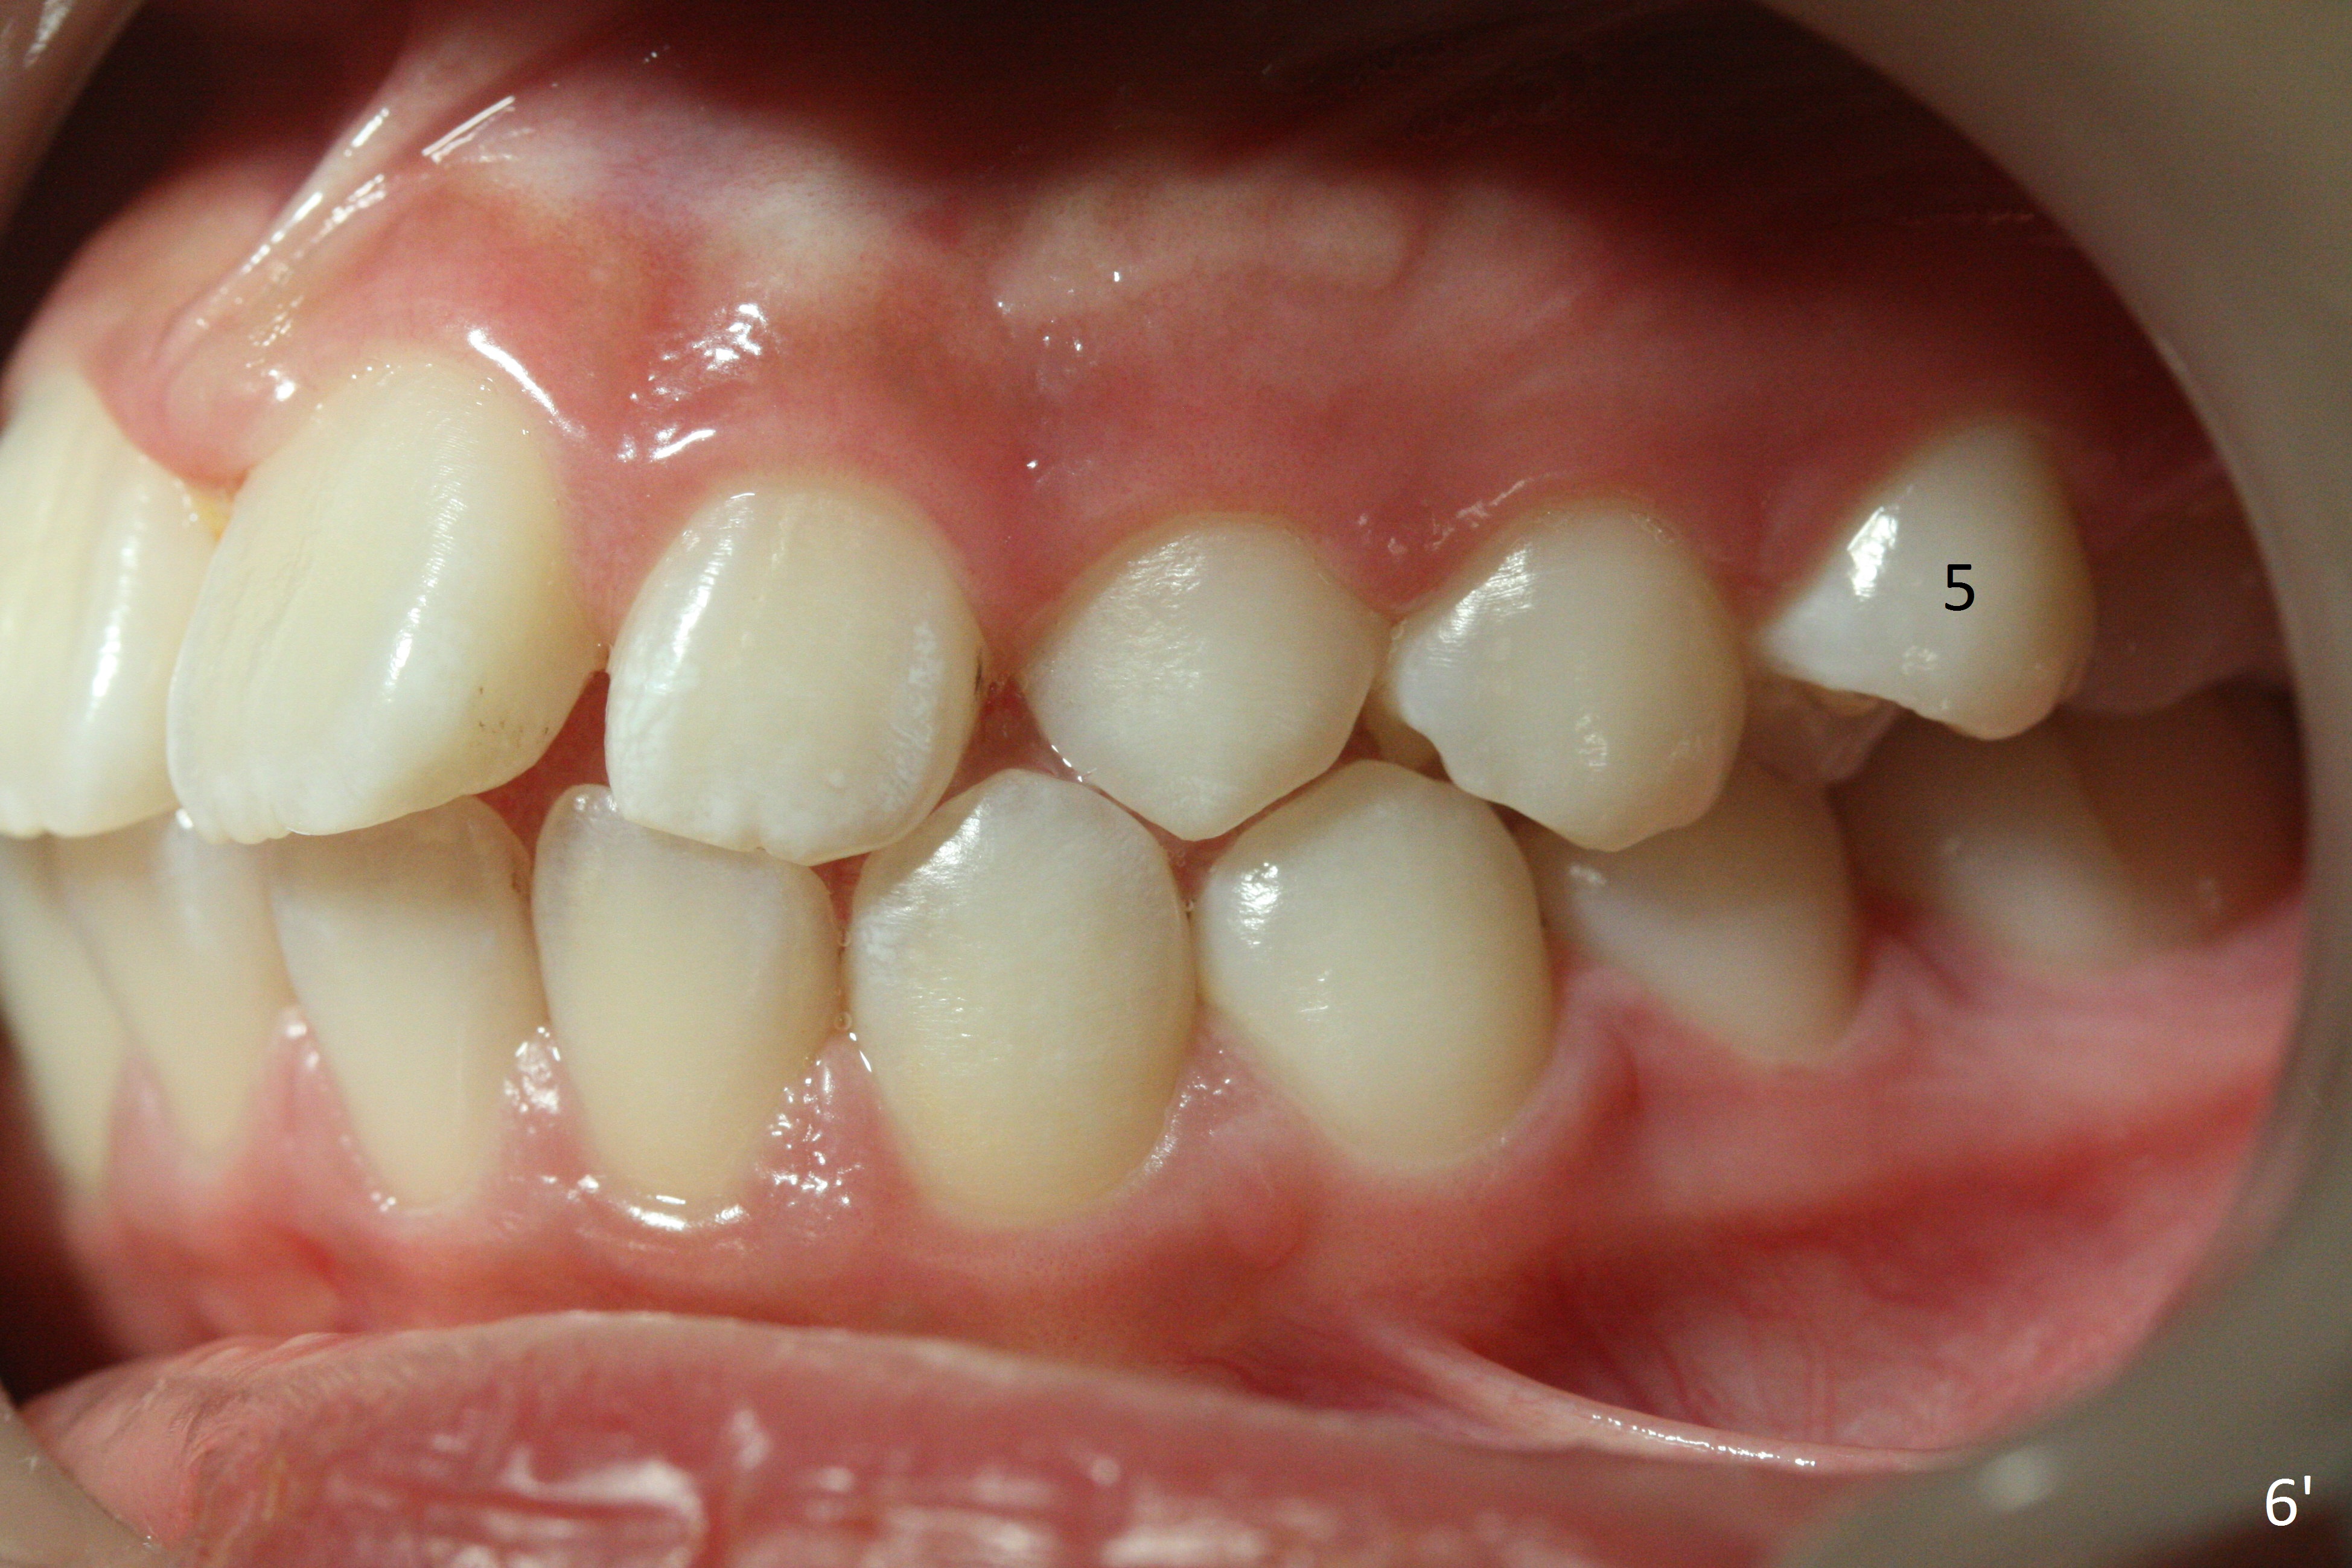

Two sisters (Sophia, 13 years old and Selina, 11) present to clinic for orthodontic treatment. Dental anomalies of Sophia include microdontia of the upper lateral incisors and congenital missing of the upper right permanent canine (Fig.5,6). For Selina, the upper right lateral incisor (Fig.5') and the upper left second bicuspid (Fig,6') are in cross bite.